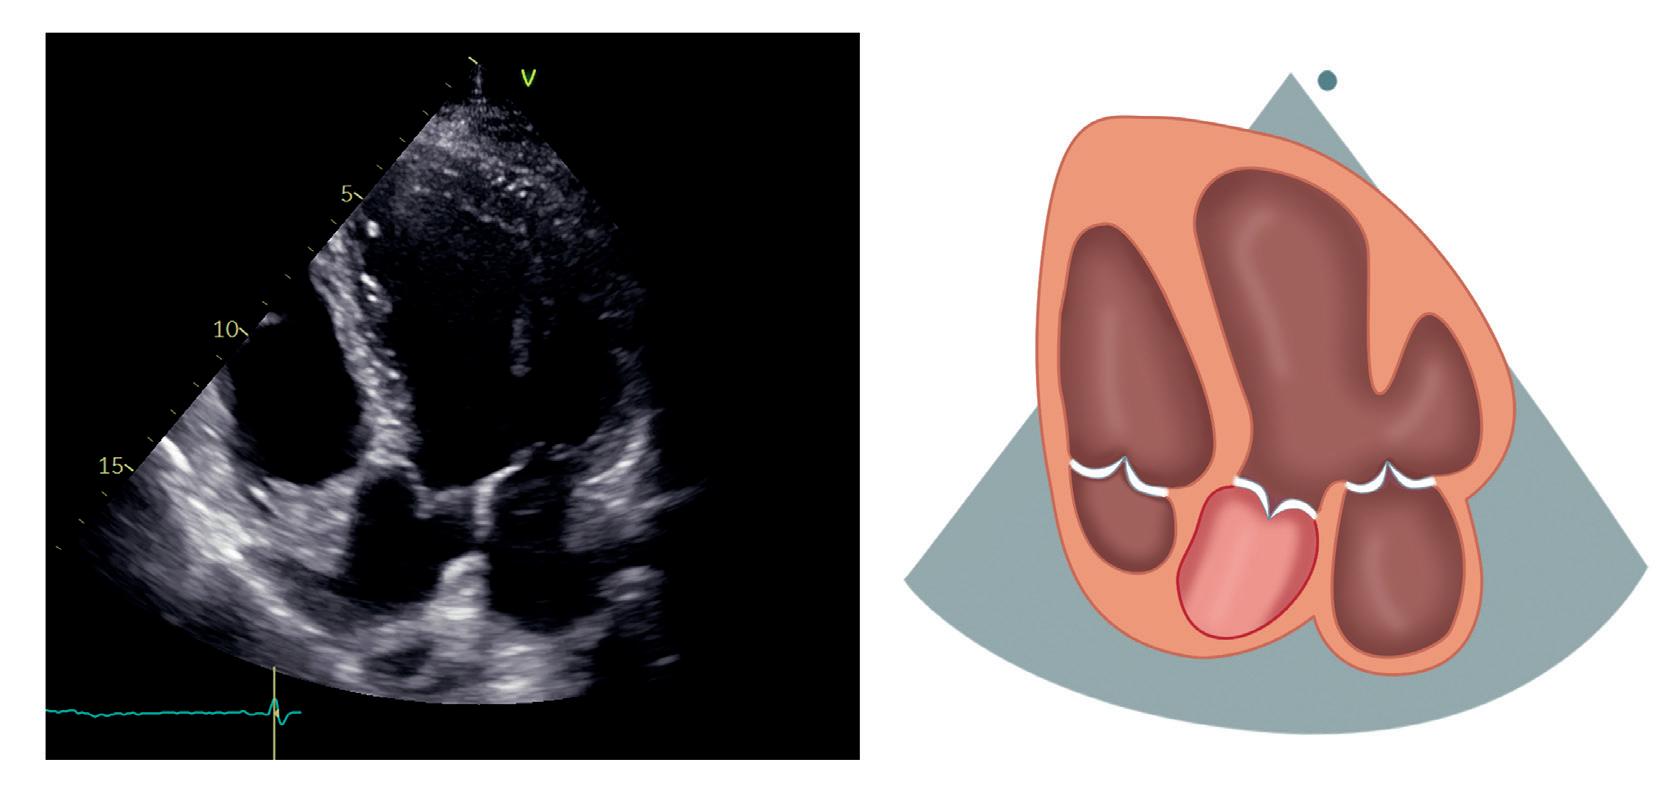

Apikal 4-kammerprojeksjon

Venstre ventrikkel skal være formet som en geværkule, og ventrikkel- og atrieseptum skal være sentralt plassert og gå rett vertikalt i bildet. Ofte må plasseringen av transduseren eller pasientens leie justeres underveis for å få et best mulig bilde.

Apikal 4-kammerprojeksjon er svært nyttig og fremstiller alle fire hjertekamre, mitral- og trikuspidalklaff (figur 2.6).

Venstre ventrikkel med inferiore septum, apex og anterolateralveggen ligger øverst til høyre. Høyre ventrikkel ligger øverst til venstre. Atriene ligger nederst i bildet. Mitralklaffen er plassert mellom venstre atrium og ventrikkel med det fremre seilet til venstre og det bakre til høyre. Trikuspidalklaffen ligger mer apikalt enn mitralklaffen. Det septale seilet ses ved septum, mens det andre trikuspidalseilet i bildet er enten det fremre eller det bakre. Lungevenene ses munne ut i venstre atrium, eventuelt visualiseres de bedre med litt justering av transduserens plassering eller vinkling. Dersom vi er heldige kan tre av venene ses i standard apikal 4-kammerprojeksjon, mens den siste, som er den øvre høyre venen, kan ses med litt

Høyre ventrikkel (HV) Høyre atrium (HA) Ventrikkelseptum (IVS) Venstre ventrikkel (VV) Trikuspidalklaffen (TK) Venstre ventrikkel (VV) HA HV IVS MK TK IAS VA VV Mitralklaffen (MK) Atrieseptum (IAS) Venstre atrium (VA) Figur 2.6: Apikal 4-kammerprojeksjon

Tabell 2.5 lister opp sentrale målinger i apikal 4-kammerprojeksjon.

Tabell 2.5: Sentrale målinger i apikal 4-kammerprojeksjon

Målinger i apikal 4-kammerprojeksjon

Venstre ventrikkels volum og ejeksjonsfraksjon (EF) (Simpsons metode)

Venstre atriums volum (Simpsons metode, endesystolisk)

Høyre atriums volum (endesystolisk)

Pulset doppler ved tuppen av de åpne mitralseilene i diastolen

TAPSE (M-modusekkokardiografi)

Kontinuerlig doppler over trikuspidalklaffen

Pulset doppler i en lungevene (målevolumet plassert 10 mm fra innmunningen til venstre atrium)

Vevsdoppler i laterale og septale mitralannulus